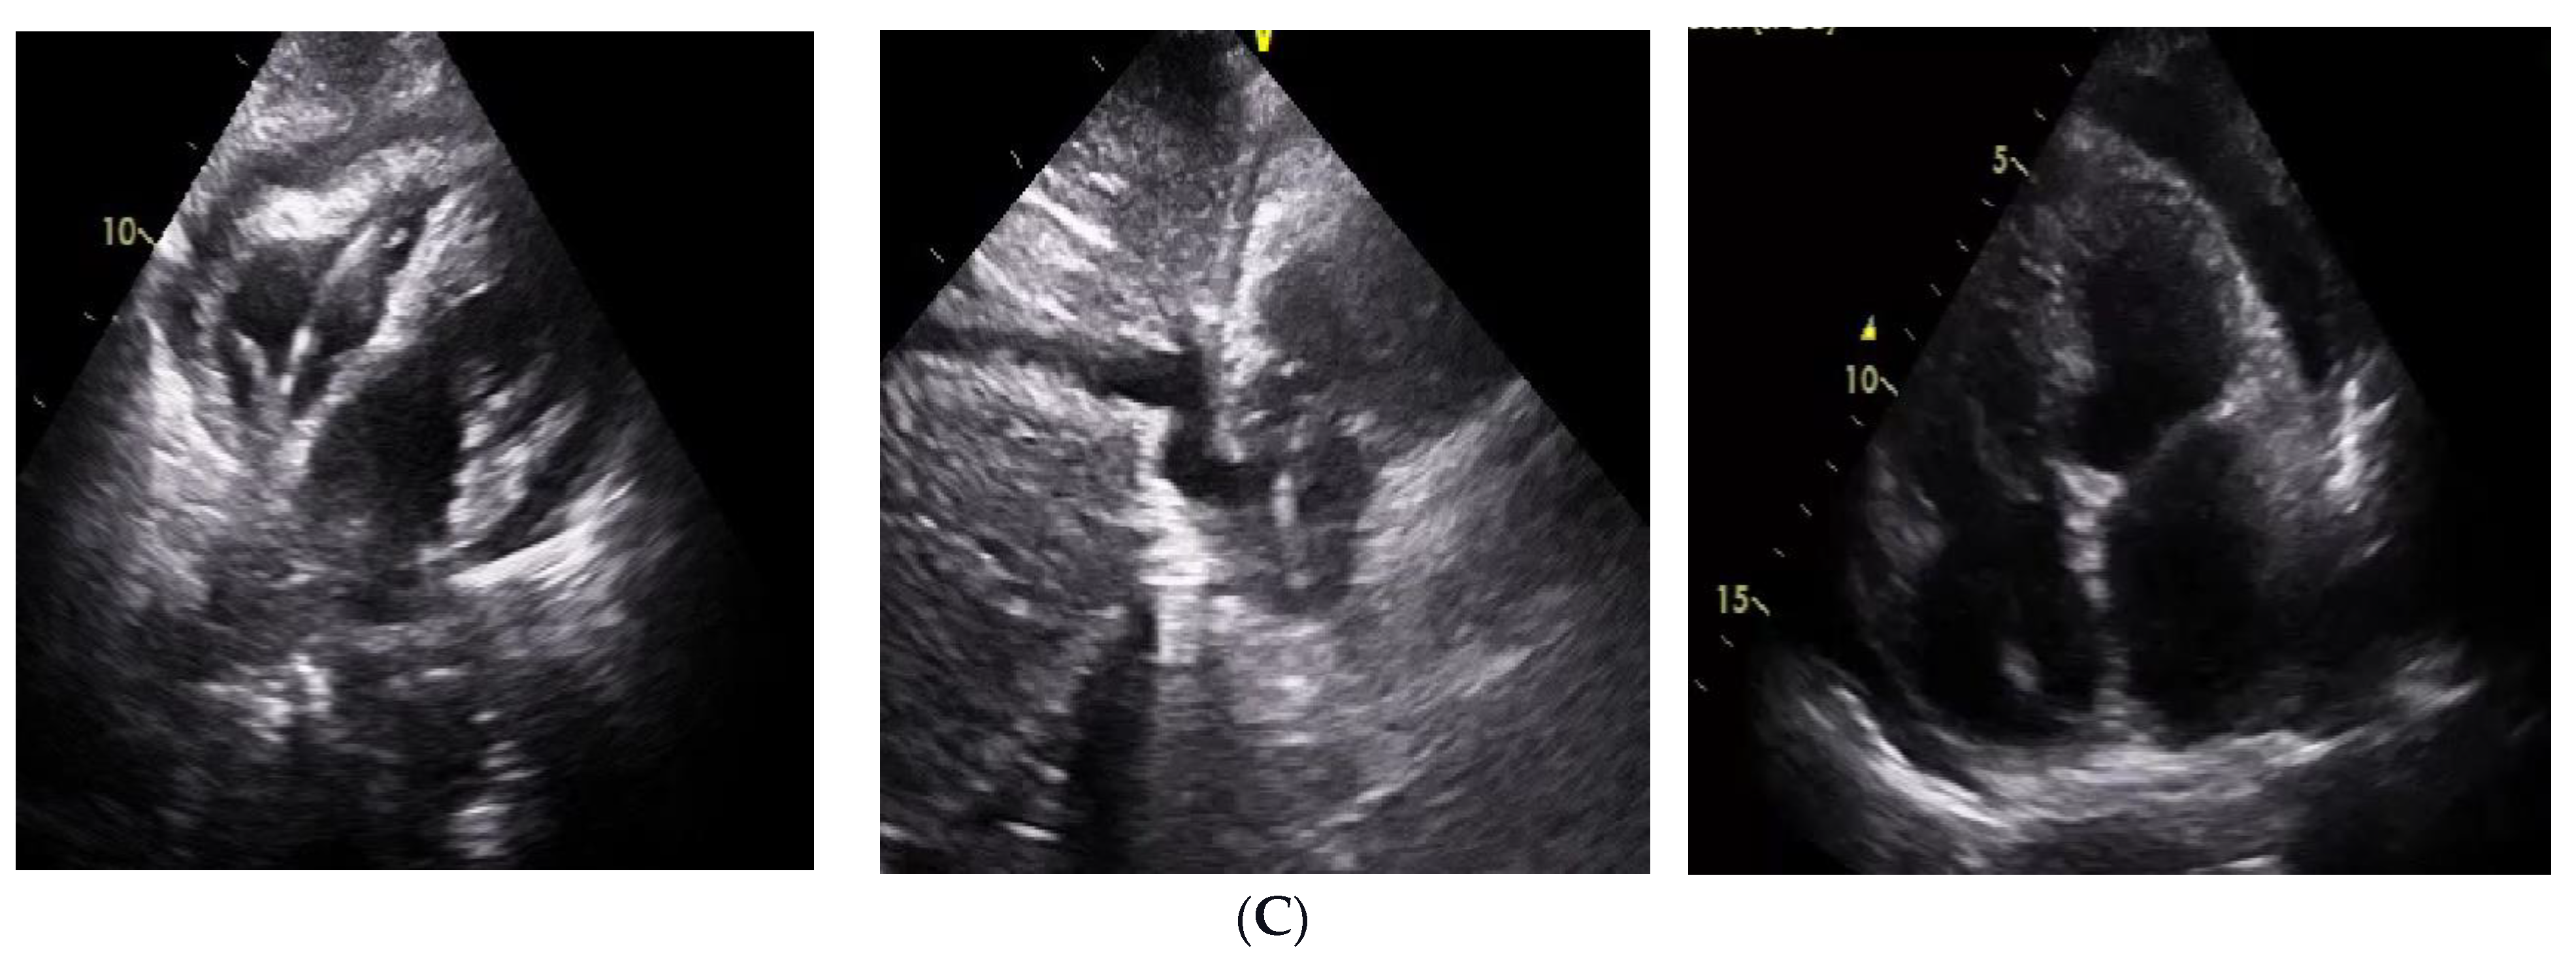

Dual Chamber Pacemaker Implant in Coronary Sinus Leading to Several Complications